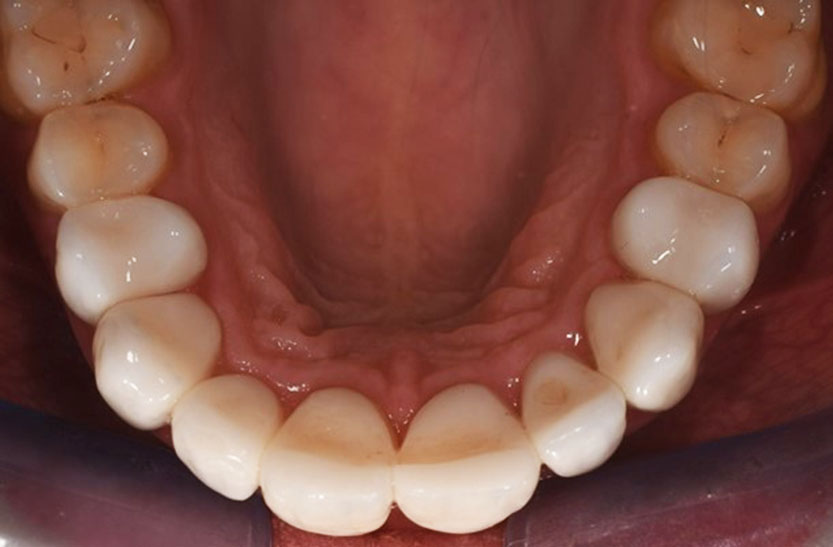

Figur 8. Resultat etter revisjonsbehandling. Bildet viser nye sementerte kroner fra 14 til 24. På enkelte tenner sees irritasjon i gingiva etter nylig fjerning av sementoverskudd. Bilde tatt ved Spesialistutdanningsklinikken ved IKO, UiB.

Etter konsultasjonstimen innledes en revisjonsbehandling, som strekker seg over et halvt år. Åtte nye kroner ble fremstilt med best mulig funksjon og estetikk (figur 8). Pasienten beskrives som svært fornøyd med resultatet.

Pasienten fikk revidert hele arbeidet ved Spesialistutdanningsklinikken på Institutt for klinisk odontologi ved UiB. Revisjonsarbeidet inkluderte tre rotfyllinger (tann #11,12,14) og fremstilling av åtte nye kroner (figur 8). Ved konsultasjonstimen fant behandlende tannlege indikasjoner for revisjon av kronene. Ifølge journalnotat beskrives funnene slik: «Kronene 14-24 er voluminøse, lange og maskuline. Tennene står ikke i stil til resttannsettet. Dårlig estetikk og fargevalg. Tette approximalrom, vanskeligheter med renhold. Papiller interdentalt er borte. Akseretning på kroner er skjev i forhold til ansiktet. Kronene bør revideres. Gingivale forhold bør prøves å formes ved hjelp av midlertidige kroner».